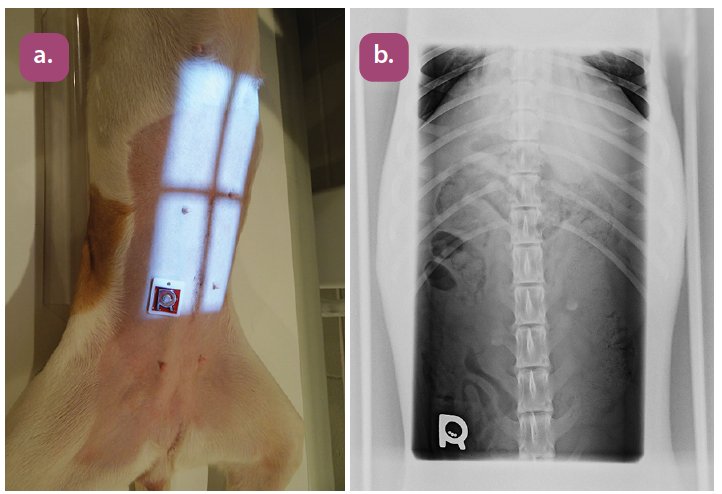

ventrodorsal lumbar spine projection

lateral lumbar spine projection

ventrodorsal lumbosacral projection

lateral lumbosacral projection